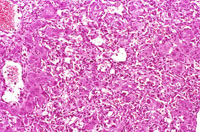

This hemangiosarcoma is poorly demarcated from surrounding parenchyma and consists of dilated blood-filled spaces and sheets of proliferating endothelial cells.